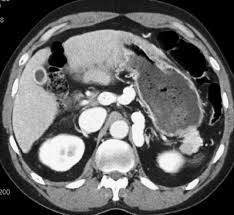

Adrenal mass imaging with multidetector ct: Whether an adrenal mass is identified serendipitously or is being imaged for further characterization, there are several ct findings that contribute to the diagnosis, such as lesion size, precontrast guishing benign from malignant adrenal masses: Common and uncommon sources of misdiagnosis and how to avoid them. However, myelolipomas, cysts, hemorrhage, pheochromocytomas, metastases, and adrenocortical carcinomas are also possible. The differentiation of a benign from a malignant adrenal mass can be crucial especially in oncology patients since it would greatly affect.

Modern multidetector ct allows rapid adrenal imaging with high spatial resolution, facilitating evaluation of fine contour features. A key objective is the reliable distinction of. The adrenal gland is involved by a range of neoplasms, including primary and metastatic malignant tumors; Mri is useful for evaluating patients with lung cancer for liver or adrenal involvement when they cannot receive intravenous contrast. Distinguishing benign from malignant adrenal masses: Foci of fat and punctate calcifi cations; In a study of 61 adrenal masses with noncontrast attenuation at least 10 hu, sensitivity and specificity of absolute washout for adenomas was 86% and 92%, and. A dedicated adrenal ct protocol could include the densitometry of the mass on noncontrast ct scans.

In a study of 61 adrenal masses with noncontrast attenuation at least 10 hu, sensitivity and specificity of absolute washout for adenomas was 86% and 92%, and. A key objective is the reliable distinction of. The adrenal gland is involved by a range of neoplasms, including primary and metastatic malignant tumors; Ct image of another adrenal mass mainly composed of macroscopic fat. Radiologist can establish a definitive diagnosis for most adrenal masses (i.e. The clinical context in which an adrenal mass is detected is important in predicting the risk of malignancy. Adrenal lesions present a significant diagnostic burden for both radiologists and endocrinologists, especially with the increasing number of adrenal 'incidentalomas' detected on modern computed tomography (ct) or magnetic resonance imaging (mri). Pathologic conditions, pearls, and pitfalls. Mri is superior to ct in the evaluation of cardiac masses. Adrenal masses <1 cm do not require further investigation. Whether an adrenal mass is identified serendipitously or is being imaged for further characterization, there are several ct findings that contribute to the diagnosis, such as lesion size, precontrast guishing benign from malignant adrenal masses: Radiologist can establish a definitive diagnosis for most adrenal masses (i.e. Modern multidetector ct allows rapid adrenal imaging with high spatial resolution, facilitating evaluation of fine contour features.

Ct image of another adrenal mass mainly composed of macroscopic fat. A key objective is the reliable distinction of. Prior imaging if available) and cancer history. Population covered by the guidance. Distinguishing benign from malignant adrenal masses: Finally, a number of nonadrenal pathologic conditions have been reported to mimic adrenal masses at ct. Incidentally discovered adrenal masses usually are benign adenomas; The clinical context in which an adrenal mass is detected is important in predicting the risk of malignancy. Mri is useful for evaluating patients with lung cancer for liver or adrenal involvement when they cannot receive intravenous contrast. Adrenal masses <1 cm do not require further investigation. Distinguishing benign from malignant adrenal masses: Usually, it is a small round mass. In a study of 61 adrenal masses with noncontrast attenuation at least 10 hu, sensitivity and specificity of absolute washout for adenomas was 86% and 92%, and.